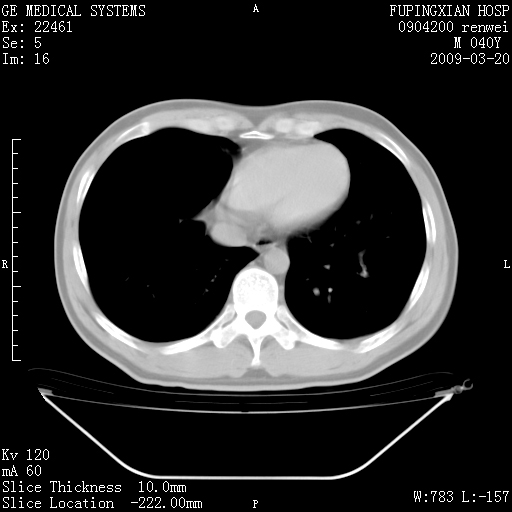

标题: CT18920:平时体健,体检时发现以下问题。 [打印本页]

标题: CT18920:平时体健,体检时发现以下问题。

右肺气肿。

右肺局限性肺气肿

右肺局限性肺气肿。

右肺局限性肺正常

右肺局限性肺气肿;[考虑黏液栓]所致。

右肺局限性肺气肿,原因?先天支气管闭锁?粘液栓?